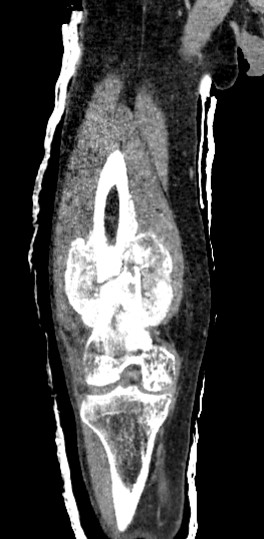

Хворий Г.58 остеосаркома стегнової кістки

Проектування та виготовлення індивідуальних аугментів для заміщення  дефектів суглобів: М, 48р, асептична нестабільність онкологічного ендопротеза . Заміщення дефекту індивідуальним аугментом та ревізійним ендопротезом , фіксація БІС, ПММА